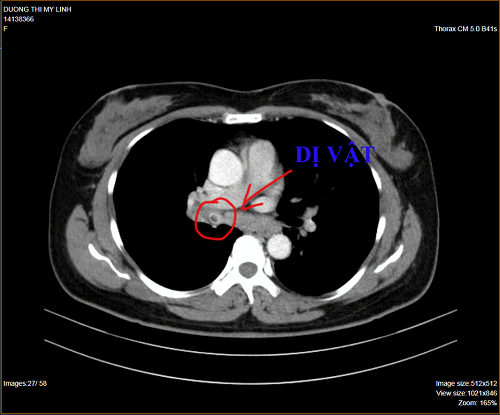

Sau khi nhập viện, bệnh nhân được các bác sĩ chỉ định chụp CT ngực , kết quả ghi nhận trong lòng phế quản thùy dưới phổi phải có một dị vật không rõ bản chất, kèm thương tổn viêm thùy giữa và thùy dưới phổi phải.

Tiếp tục tiến hành nội soi phế quản bằng ống nội soi mềm thì phát hiện dị vật có màu đen, dạng elip, kích thước khoảng 2cm, trông giống hạt sapôchê. Ngay sau đó, các bác sĩ đã tiến hành gắp dị vật ra. Sau 1 ngày, sức khỏe bệnh nhân đã hoàn toàn ổn định.